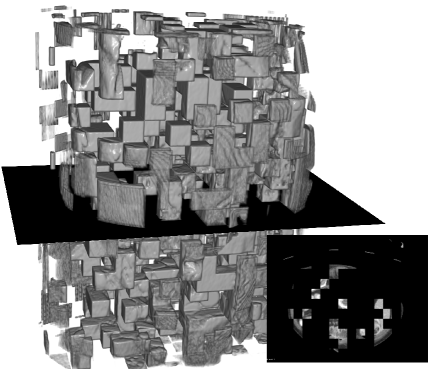

Visualization. We visualize 3D reconstruction results to check what HySparK learns in pre-training. As shown in Fig. 6, our method can almost reconstruct the different shapes of organs, bones, and other details from the very small portion of unmasked patches.

(a)

(b)

(c)

(d)

(e)

(f)